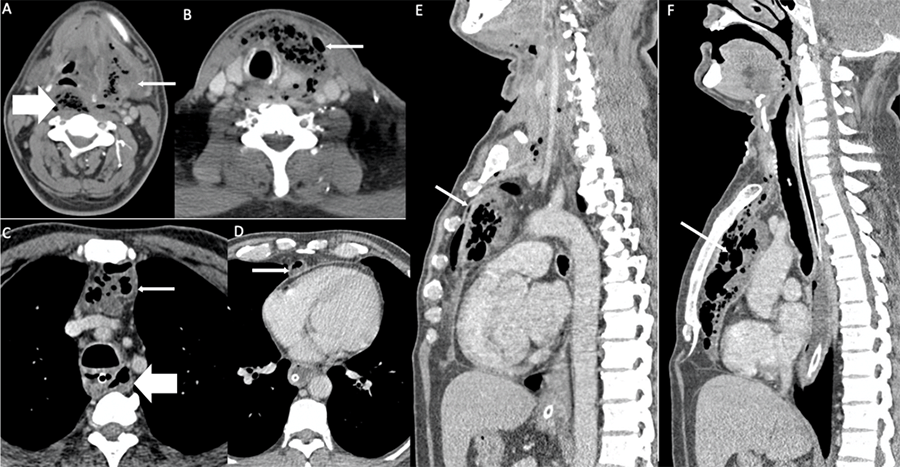

The patient showed signs of improvement initially but again developed fever and was referred to us when he developed respiratory distress and desaturation on postoperative day (POD) 9. A chest x-ray revealed a widening of the mediastinum, and a repeat CECT showed multiple collections with air-fluid levels in the whole of the anterior mediastinum as well as in retropharyngeal space (Figure 2) extending down into the danger space which lies posterior to the retropharyngeal space opening to the level of the diaphragm behind the esophagus. The predominant component of the chest collection was in the retrosternal region and extended up to the xiphisternum.

Figure 2. Axial (A‒D) and Sagittal (E‒F) Contrast-enhanced CT Images. Published With Permission

Images show collections with mottled air lucencies and air-fluid levels in left submandibular space. A) Cervical visceral space; B) pre-tracheal space and anterior mediastinum; and (C‒F) retropharyngeal space (thick arrow, A), tracking below to danger space (thick arrow, C) in chest. Large anterior mediastinal collection tracked up to xiphisternum (thin arrow).